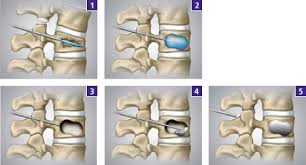

Besserung der Beschwerden bei gebeugter Körperhaltung und Hinsetzen. Es sind aber auch Operationen im Sinne einer Dekompression einer Entlastung möglich.